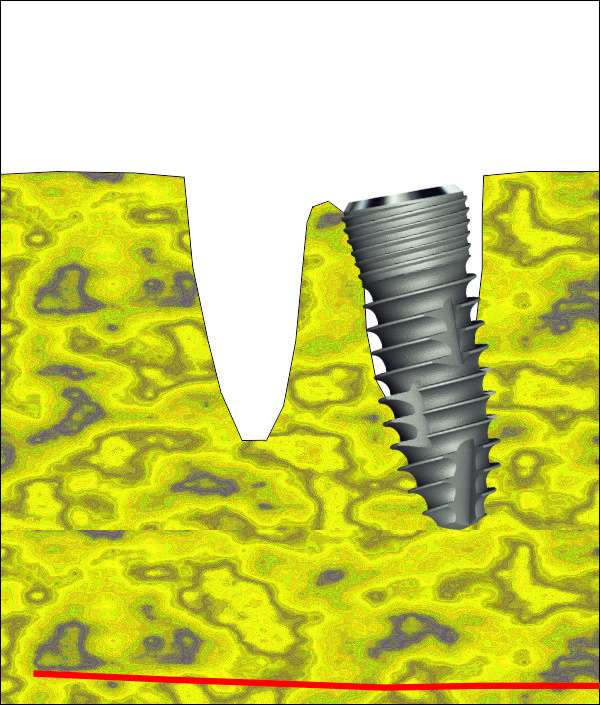

На тази снимка се вижда зъбната алвеола след изваждането на зъба. Формата на алвеолата е изключително подходяща за имедиатно имплантиране - кръгла, без междукоренови прегради, с добре запазени костни стени. Вестибуларно се вижда костен израстък, който бързо би се лизирал ако не се постави имплантат - всяка структура в организма, която не е подложена на функционално натоварване, започва да атрофира много бързо. Поради това всички автори в световната литература са единодушни за един факт: имедиатното имплантиране предпазва от костна загуба поради липсата на време за афункционална атрофия. В този ред на мисли описаният случай на имедиатно имплантиране има много по-добра прогноза, отколкото ако се изчака оздравяването на екстракционната рана.